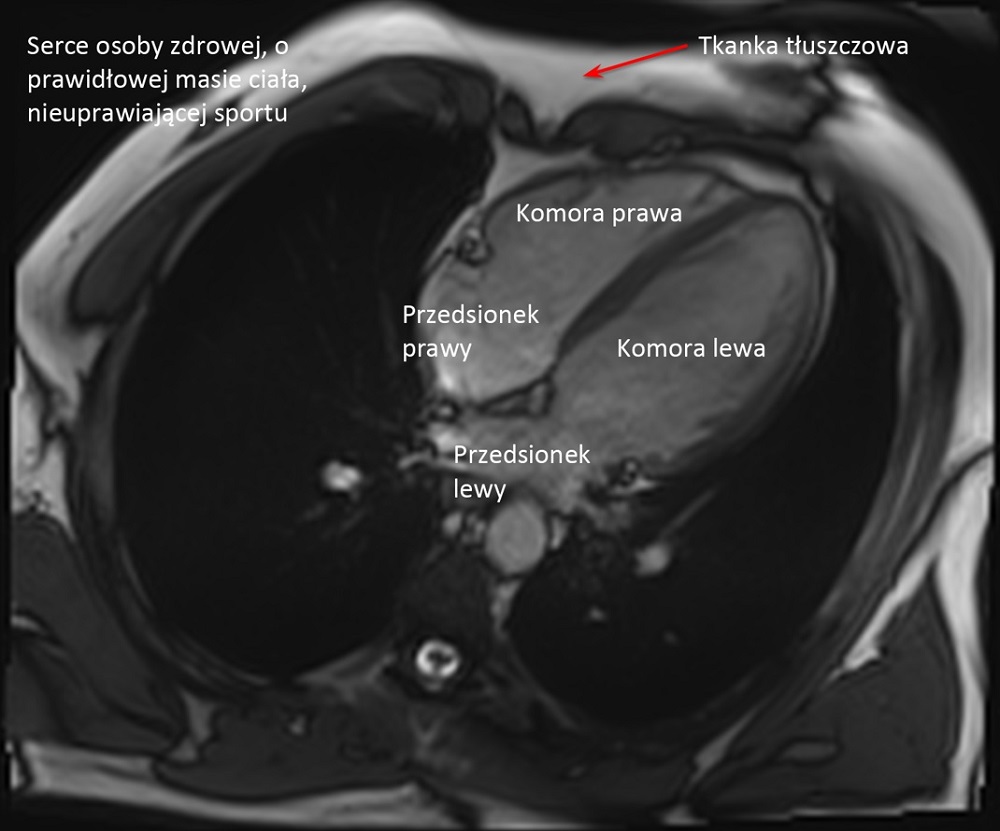

W porównaniu do grupy kontrolnej, czyli mężczyzn w tym samym wieku nie uprawiających sportu, nie stwierdziliśmy żadnych cech uszkodzenia mięśnia sercowego czy anomalii w funkcjonowaniu układu krążenia, za to większość parametrów była znacznie korzystniejsza: cholesterol był niższy, tkanka tłuszczowa mniejsza, lepsze ciśnienie krwi. To wszystko pokazuje, że ultra jest korzystne dla zdrowia serca.

Obu komór i obu przedsionków. One wszystkie powiększają się symetrycznie. Grubieje także trochę mięsień, natomiast raczej nie poszerza się aorta. Kurczliwość mięśnia sercowego w spoczynku może być na granicy dolnej normy, bo ono wtedy odpoczywa, natomiast w wysiłku radzi sobie i reaguje znakomicie.